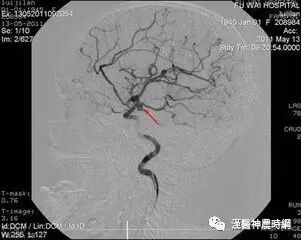

先天性脑动脉瘤好发于脑底动脉环分叉处及其主要分支,约85%的先天性动脉瘤位于Willis动脉环前半环颈内动脉系统,即颈内动脉颅内段,大脑前动脉,前交通动脉,大脑中动脉,后交通动脉的后半部,其中以颈内动脉的虹吸部发生最多,大脑前动脉及前交通动脉次之,大脑中动脉再次之,左右两侧半球发病率相近,右侧稍多于左侧,其中大脑前动脉占4.3%~9.0%,前交通动脉占9.6%~28%;椎动脉占2.3%~4.6%,基底动脉占1.7%~8.9%,综合文献中6570例动脉瘤,其分布情况如下:颈内动脉41.3%,前交通动脉26.1%,大脑中动脉20.4%,大脑前动脉7.6%,椎-基动脉4.6%。

尸检报告中与临床统计上两者的动脉瘤分布无多大差异,有人尸检统计,颈内动脉占26%,大脑中动脉占39%,大脑前动脉及前交通动脉占24%,椎-基动脉占8%,其他部位占3%,基底动脉环的后半环的动脉瘤占3%~16%,以往由于椎-基动脉造影未全面进行,故其发病率较低,现在普遍应用4条血管造影的病例中,椎-基动脉瘤的发生率占脑动脉瘤全部的15%左右。